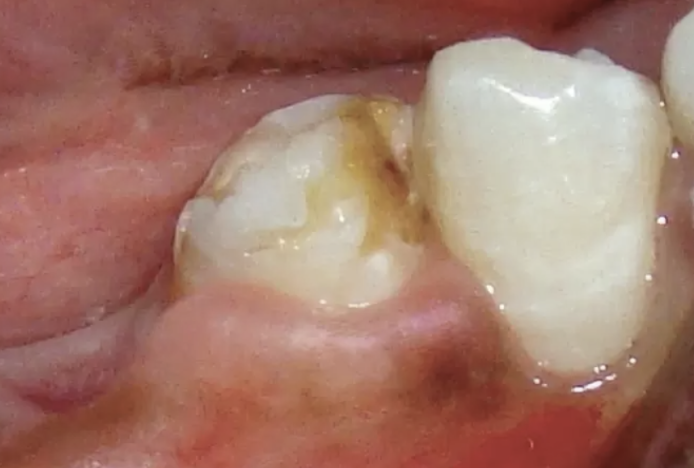

Q

Mom came into the office and said the child had the first molar extracted before the eruption of the premolar. Based on the following image, what is the likely cause for this discoloration?

A

Turner hypoplasia